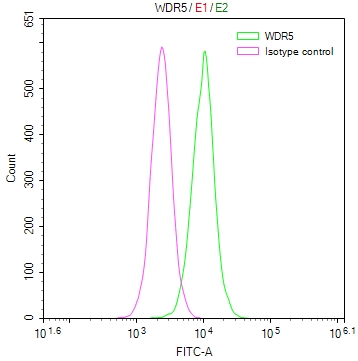

The image on the left is immunohistochemistry of paraffin-embedded Human gastic cancer tissue using CSB-PA051152(CYP2D6 Antibody) at dilution 1/30, on the right is treated with synthetic peptide. (Original magnification: ×200)